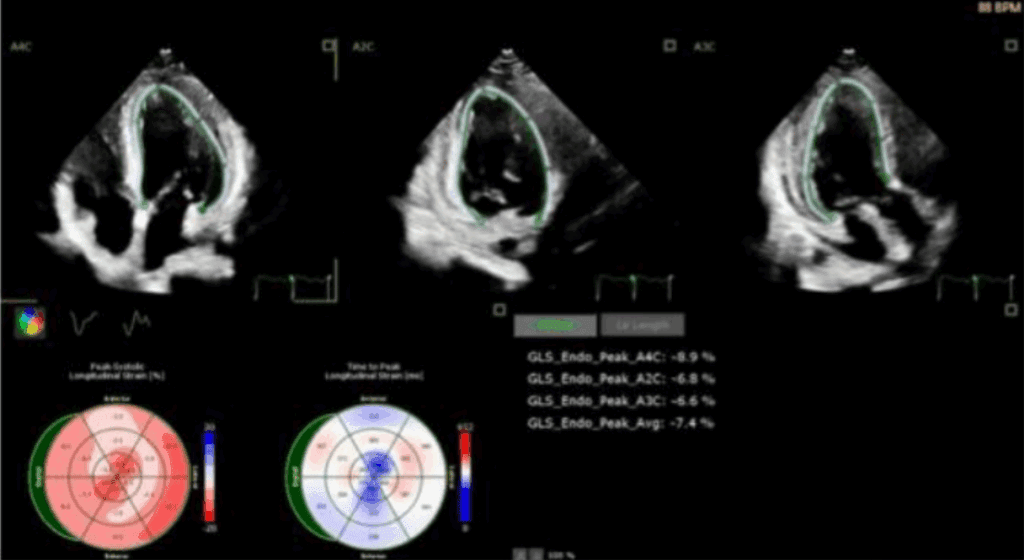

Odkształcenie mięśnia sercowego (strain) jest metodą szeroko wykorzystywaną w diagnostyce echokardiograficznej w grupie chorych z przerostem mięśnia lewej komory serca (ang. left ventricular – LV) o różnej etiologii. W tej grupie chorych standardowe przezklatkowe badanie echokardiograficzne (ang. transthoracic echocardiography – TTE) rozszerzone o pomiar odkształcenia lewej komory serca (ang. left ventricular strain – LV-GLS) ułatwia rozpoznanie, jak i pozwala na różnicowanie przyczyn przerostu LV.

W artykule przedstawiono przypadki kliniczne różnych pacjentów z chorobami układu sercowo-naczyniowego oraz przerostem mięśnia sercowego, u których pomiar odkształcenia (strain) LV istotnie ułatwia diagnostykę różnicową.